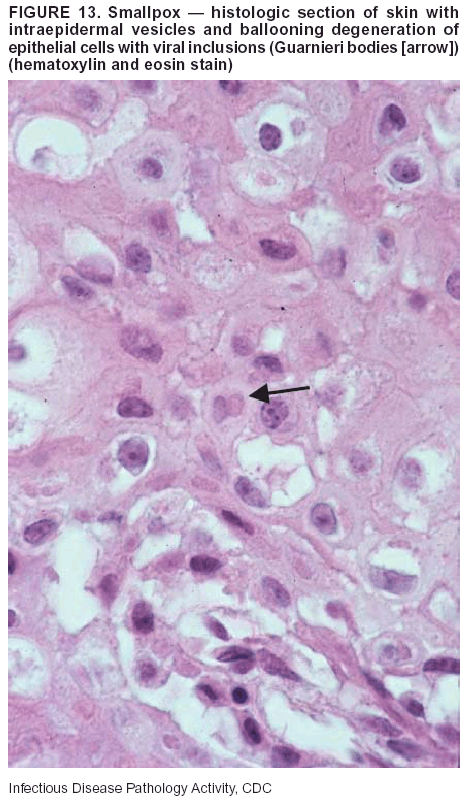

Pathologic Findings. Smallpox is an acute, highly contagious illness caused by a member of the Poxviridae family. Variola major refers to the form with a higher mortality rate, and variola minor or alastrim is a milder form. The lesions develop at approximately the same time and rate, starting in the palms and soles and spreading centrally; they first appear as macules and papules, and then progress to vesicles and umbilicated pustules (Figure 12), followed by scabs and crusts, and end as pitted scars. Occasionally, a hemorrhagic and uniformly fatal form occurs. This form has extensive bleeding into the skin and gastrointestinal tract and can be grossly taken for meningococcemia, acute leukemia, or a drug reaction (42). Microscopically, the skin exhibits multiloculated, intraepidermal vesicles; ballooning degeneration of epithelial cells; intracytoplasmic, paranuclear, and eosinophilic viral inclusions (i.e., Guarnieri bodies) (Figure 13); and occasionally intranuclear viral changes. Secondary infections (e.g., bronchitis, pneumonia, and encephalitis) can complicate the clinical appearance (43--48).

Diagnostic Specimens. Cutaneous lesions are the most important sample for smallpox. Samples should include fluid from vesicles to be studied by electron microscopy, and skin samples fixed in formalin for histopathology and immunohistochemistry. Performing a complete autopsy with histologic sampling of multiple organs will help determine the extent and distribution of the virus, as well as the occurrence of secondary infections.

Diagnostic Tests. Electron microscopic studies of vesicle fluid or skin samples can identify characteristic viral particles (Figure 14). IHC studies have demonstrated the virus in the epithelial cells and in the subjacent fibroconnective tissue.